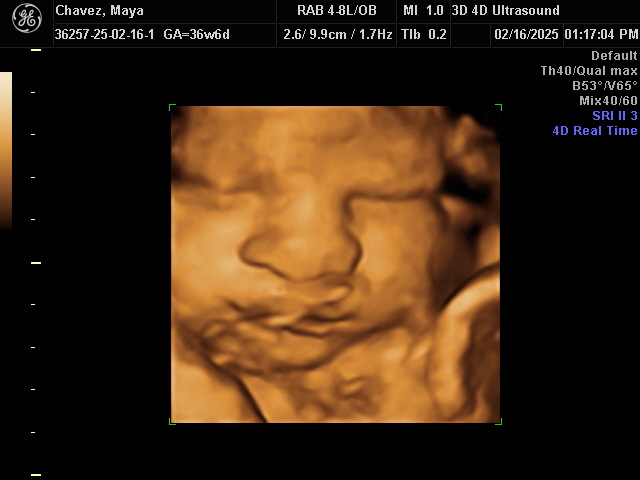

Our Gallery

Explore beautiful moments captured during our 3D and 4D sessions.